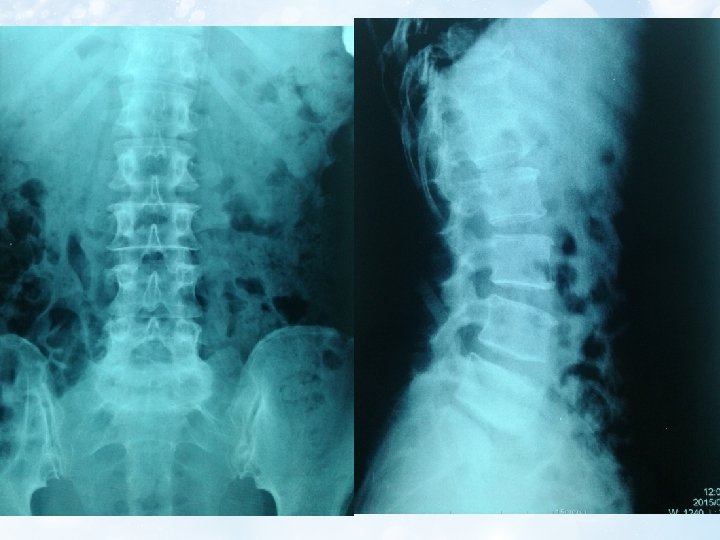

6. MRI Thoái hóa đốt sống thắt lưng và đĩa đệm L 3/4, L 4/5, L 5/S 1 Thoát vị đĩa đệm L 5/S 1 trung tâm chèn ép bao màng cứng và chèn rễ thần kinh cũng mức 2 bên Thoát vị Schmorl S 1 Tủy bám thấp, theo dõi viêm tủy cắt ngang D 11 L 2

b. Chẩn đoán phân biệt tổn thương do chèn ép hay do viêm: -Sự giảm tín hiệu xung T 1 và tăng tín hiệu xung T 2 trên MRI (hình ảnh) -Dựa trên lâm sàng Dấu chứng Khởi đầu Triệu chứng bắt đầu Chèn ép tủy Từ từ O Đau kiểu rễ, diện chèn X ép giảm mất cảm giác Viêm tủy Đột ngột Nhiễm trùng X O Diễn biến Liệt co cứng nhiều O Liệt mềm-cứng X Dịch não tủy Phân ly đạm tế bào O Protein và tế bào tăng O -Trên MRI đồng thời có hình ảnh tăng tín hiệu đặc trưng cho viêm tủy đồng thời cũng có sự chèn ép rễ L 5/S 1 do thoát vị đĩa đệm. Tuy nhiên với sự chèn ép rễ như vậy không thể khiến bệnh nhân liệt hoàn toàn về cả cảm giác, vận động và phản xạ tự động được.

3. CHẨN ĐOÁN • Bệnh chính: Viêm tủy cắt ngang cấp nguyên phát, thể lan rộng theo chiều dọc. T 11 -ASIA A đã hồi phục một phần hiện tại đánh giá L 1 ASIA D • Bệnh kèm: Thoát vị đĩa đệm kiểu trung tâm chèn ép rễ L 5 -S 1